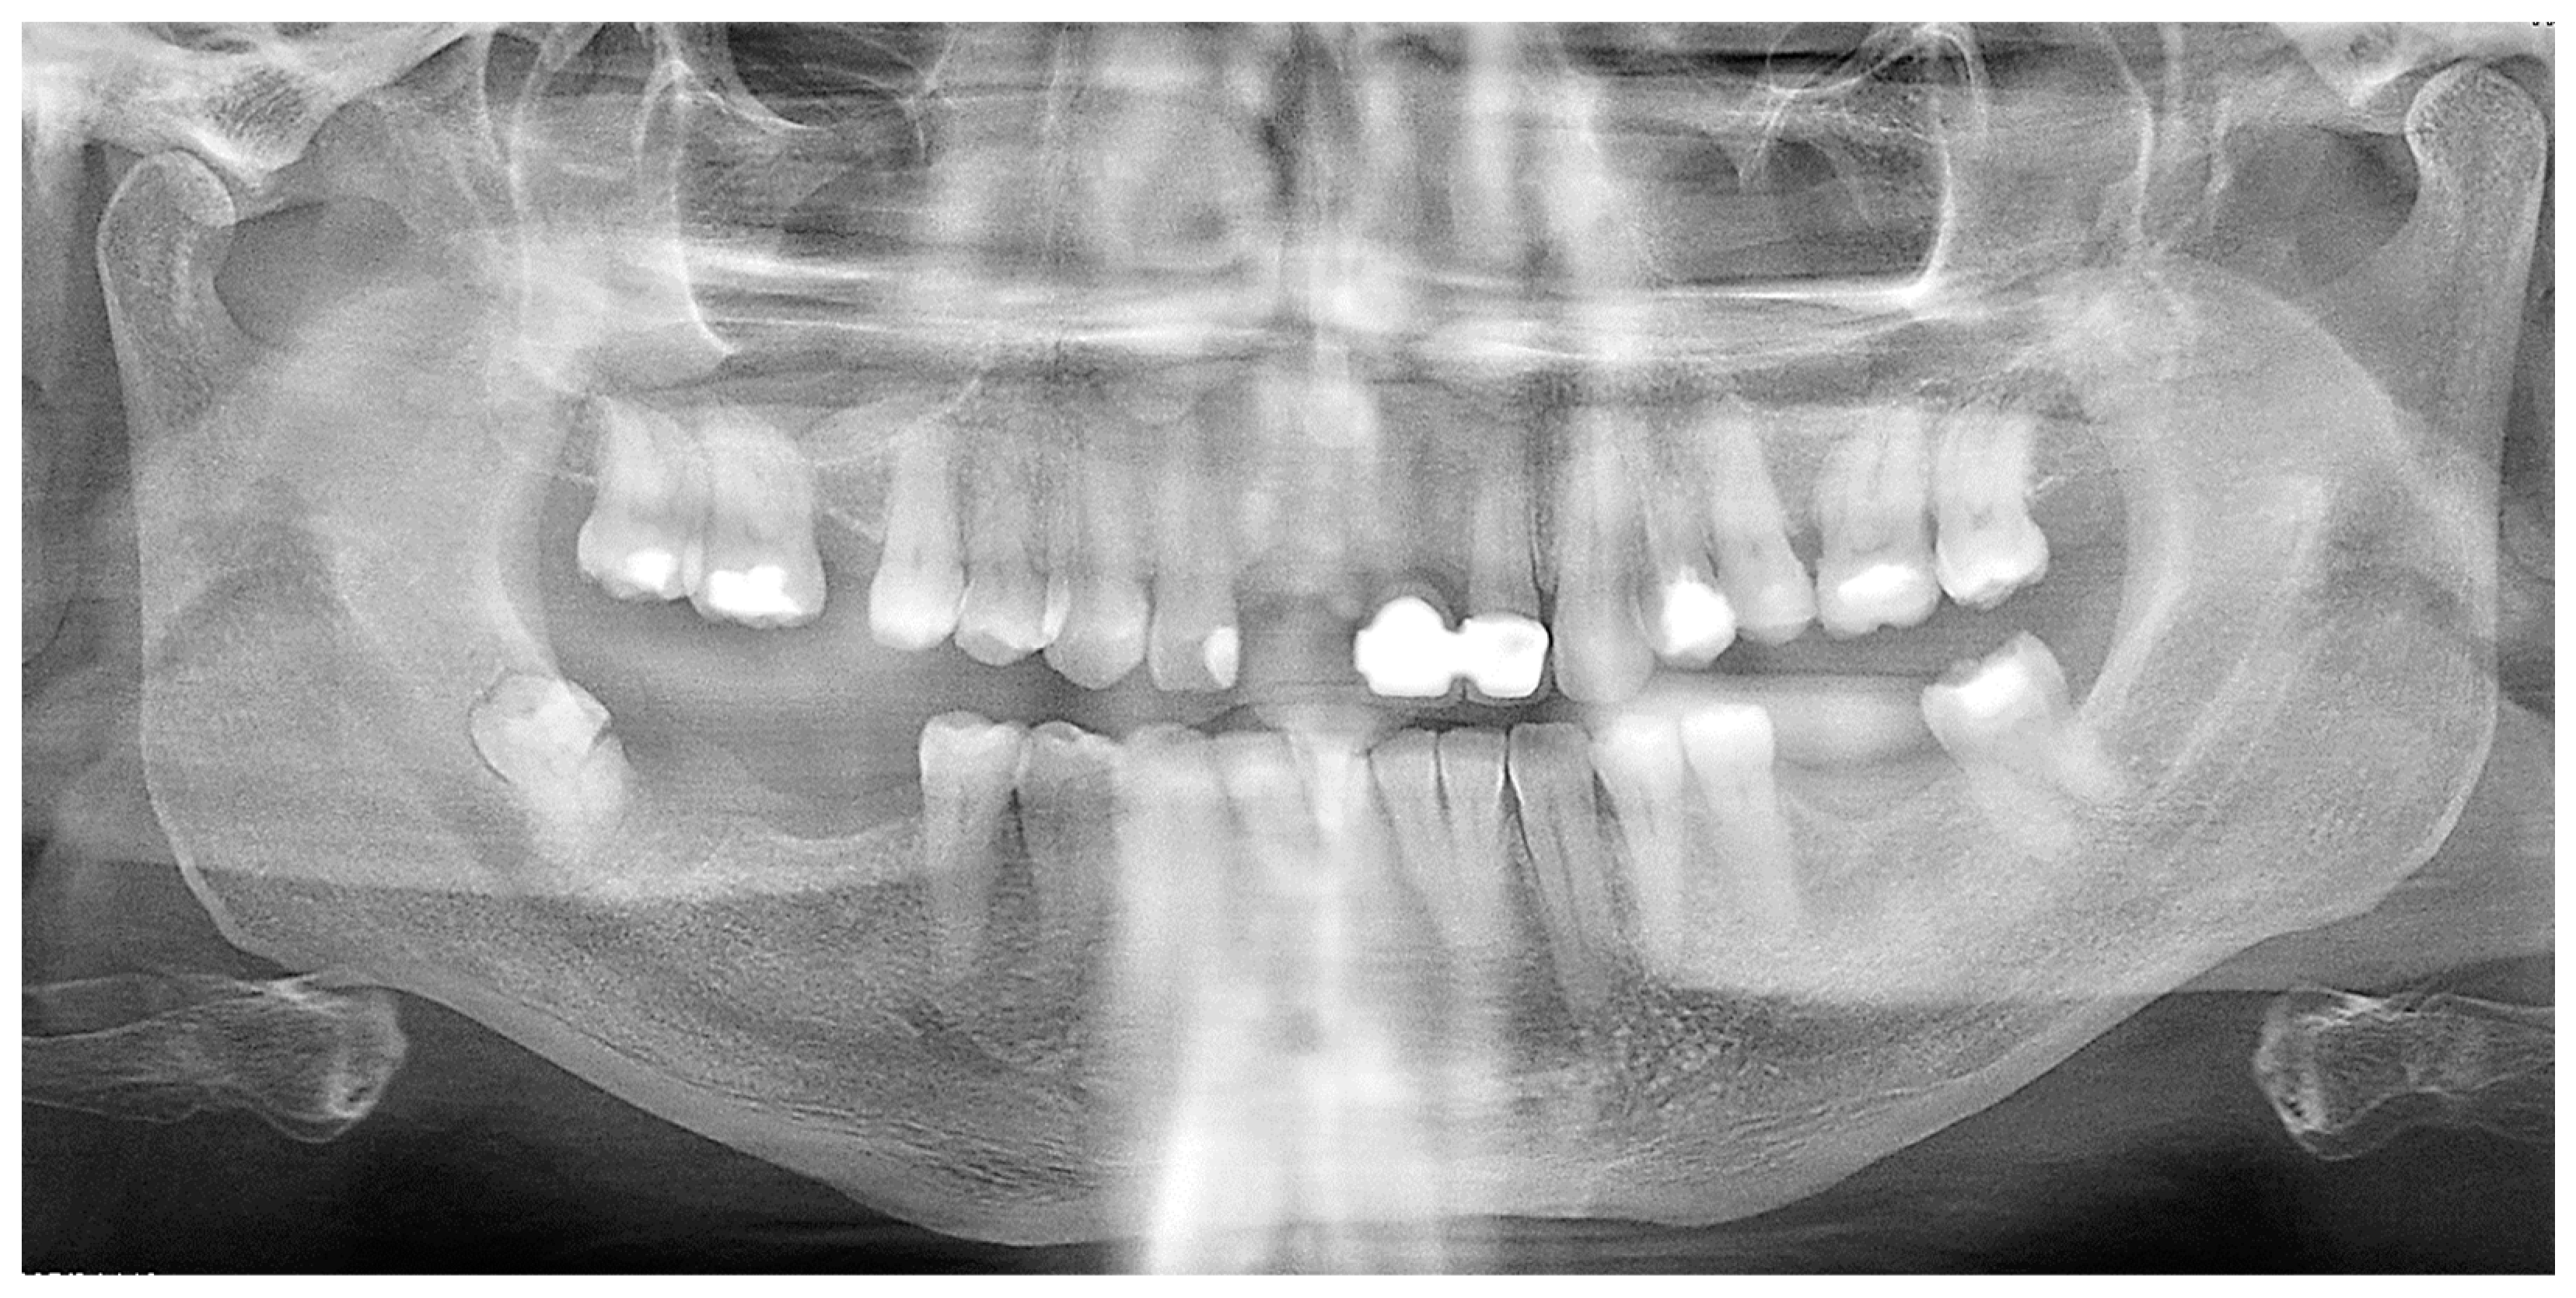

2. Detailed Case Description

- Damage to wisdom teeth should be considered as a possible cause of facial infection even if they have not erupted.